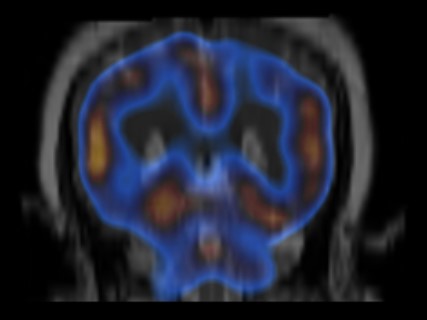

Brain hypoperfusion can be seen on a SPECT brain scan as areas of decreased blood flow.

Brain SPECT Images